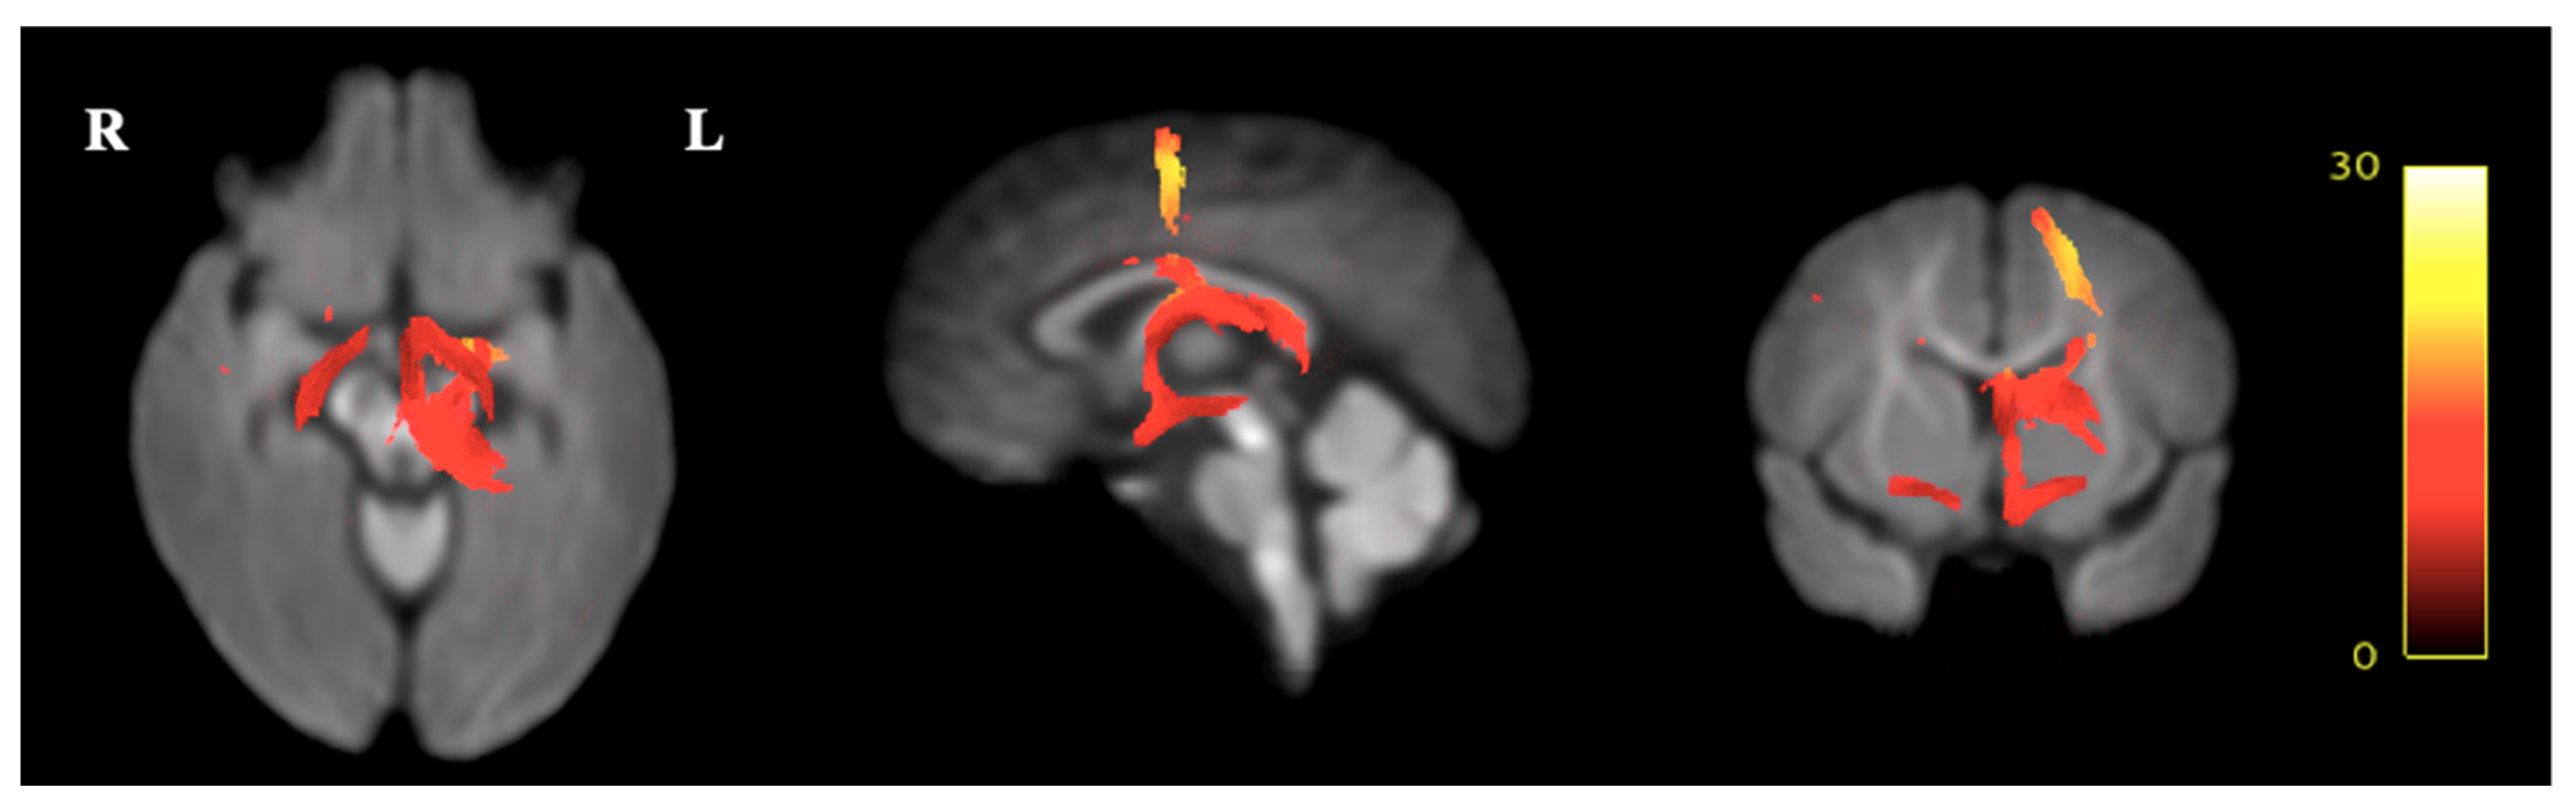

3.4. Fixel-Based Diffusion